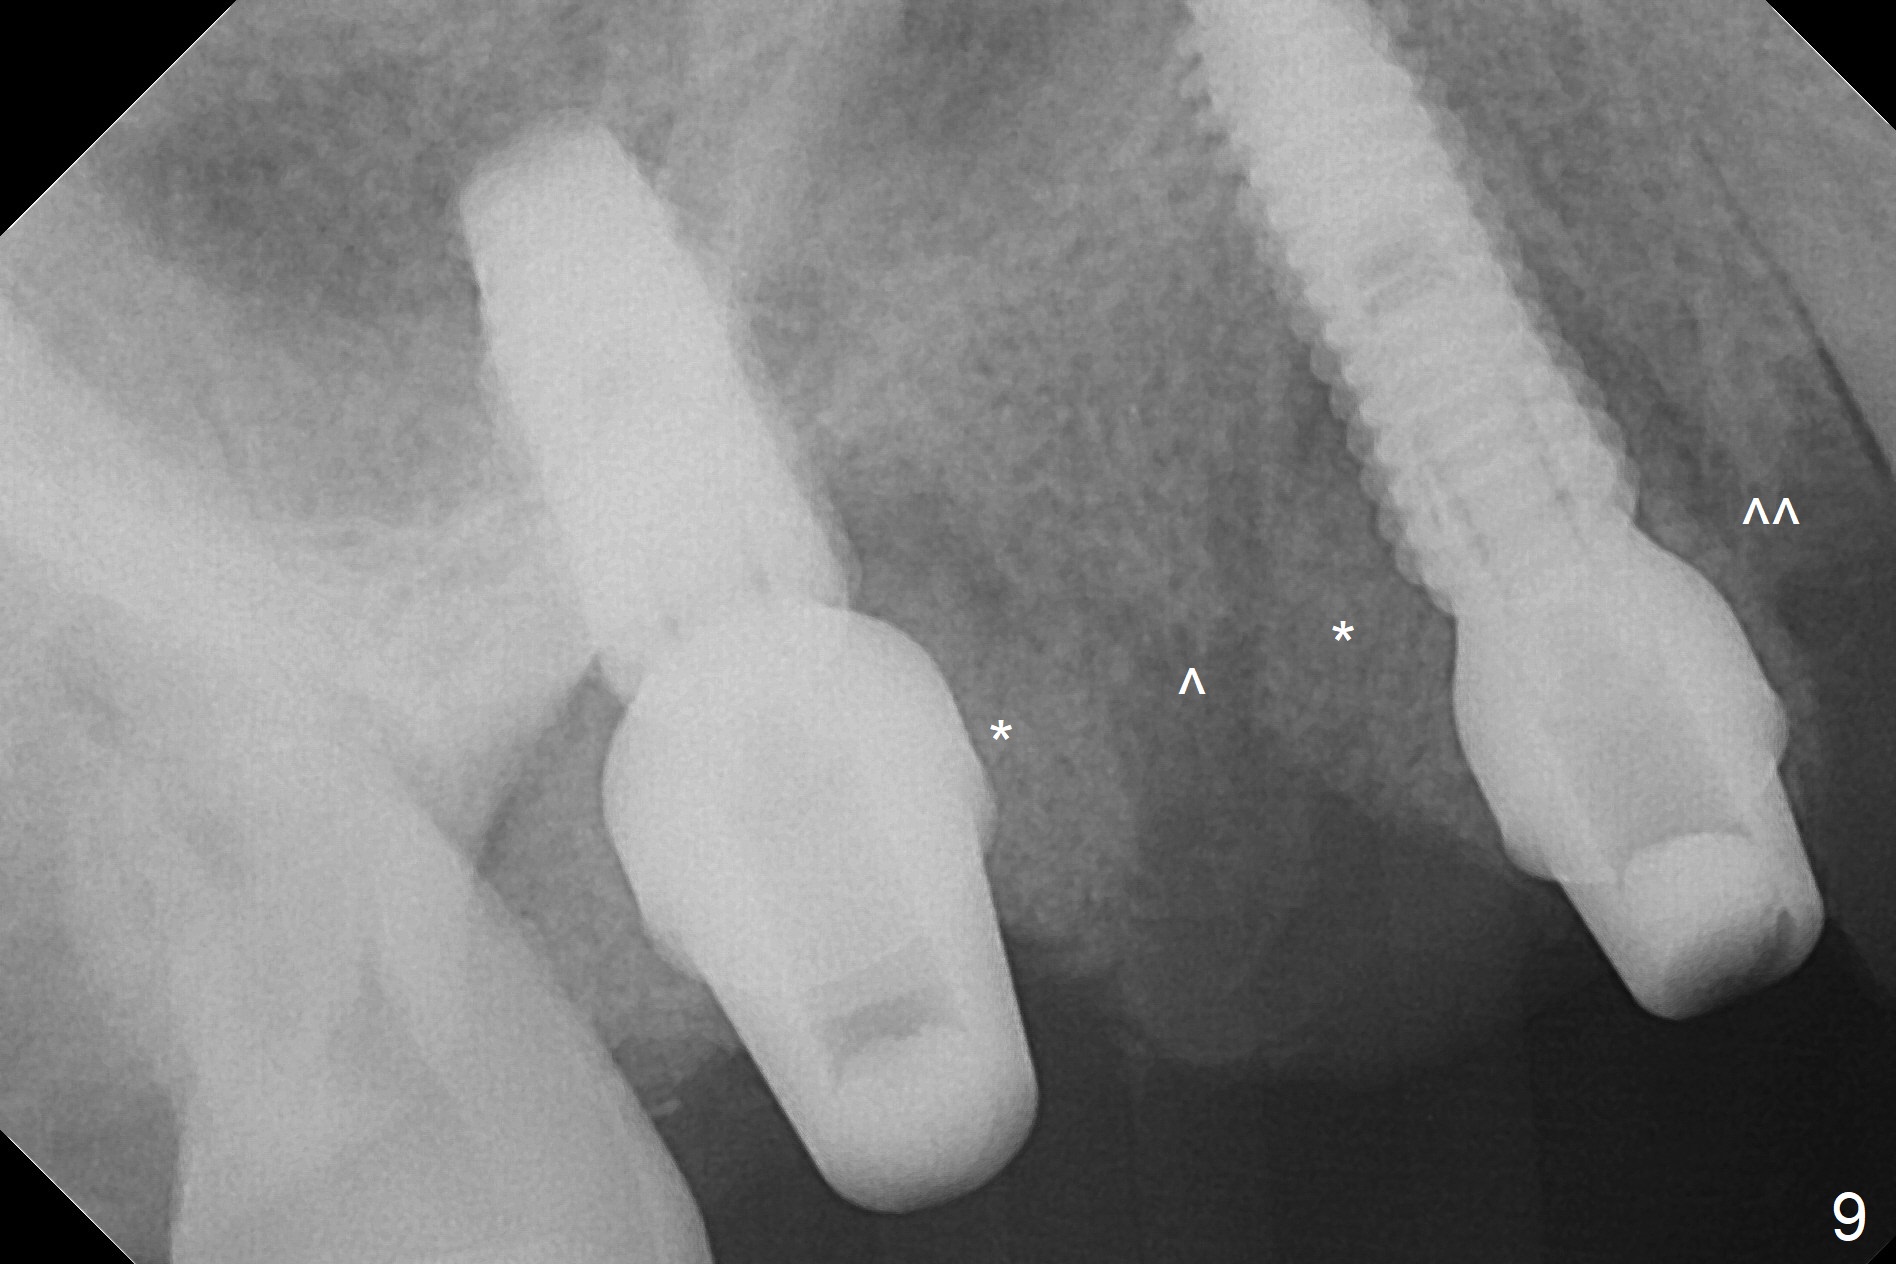

The 36-year-old man (ex-smoker, quit for 4-5 years) insists upon #3 and 5 extraction first for implants, in spite of more severe infection at #7, 14,19,30 (Fig.1-4). The gingiva around #23-26 implants is healthy 3 weeks postop (Fig.5). The initial depths at #3 and 5 are 8.5 mm (bone-level) and 18 mmm (gingiva-level (13 mm (implant length) + 5 mm cuff), respectively. When a drill penetrates the sinus floor, confirm the depth. After use of 3.8 mm drill, 4.5 mm tap drill is inserted at #3 without stability, while a 4.5x13 mm implant is placed at #5 with primary stability (Fig.6,7). Then a 5x11.5 mm is placed at #3 subcrestal proximally after sinus lift with Vanilla graft (without sinus membrane perforation; Fig.8). The implant at #5 is seated ~1 mm deeper (subcrestal mesially (^^); supracrestal distally (^)); allograft is placed around the implants prior to insertion of 6.5x7(5) and 5.5x4(5) mm abutments; last more allograft is added (Fig.9 *, 10). The implants seem to have been osteointegrated 4.5 months postop (Fig.11,12). The gingiva is healthy around the implants without bone loss 3 months post cementation (Fig.13,14).